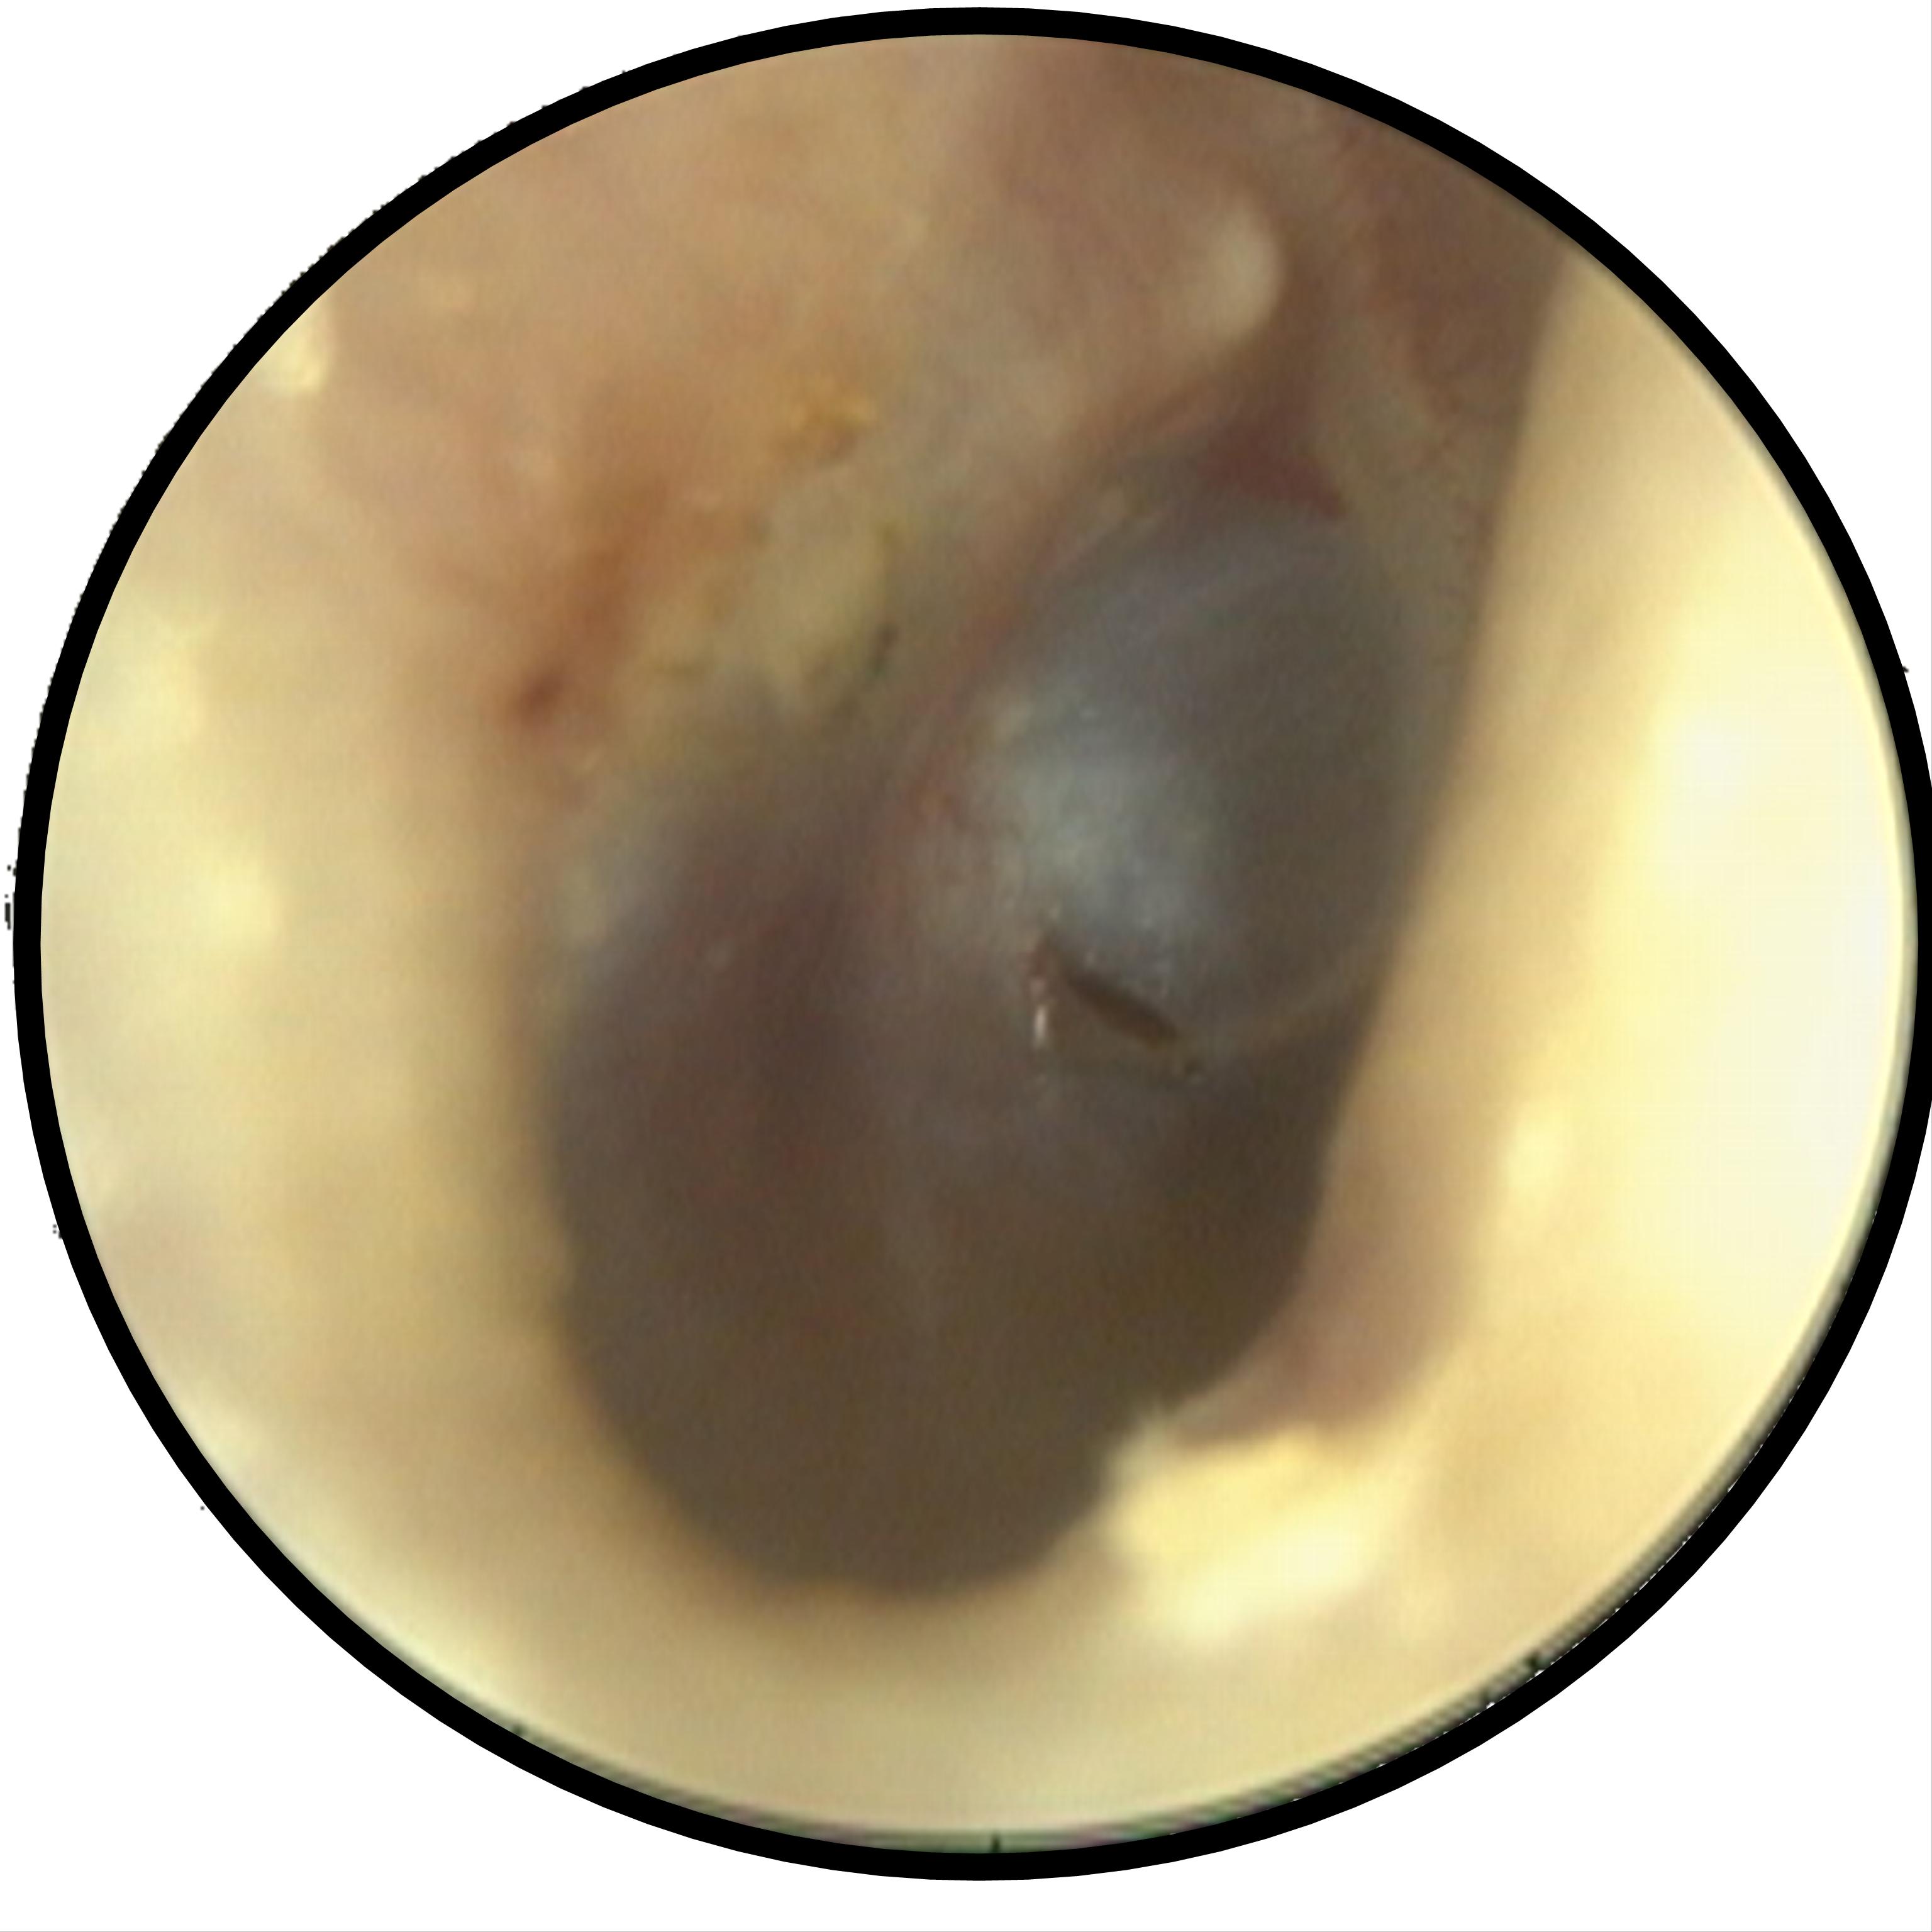

下圖說明:就醫時,該患者右側耳膜上面已有一個小洞,見到該小洞以下的耳膜呈現淡黃色,還有氣泡,原來是罹患了急性積液性中耳炎

就醫時,我發現她右側外耳道相當地乾淨,完全沒有耳垢,但耳膜上面已有一個小洞,見到該小洞以下的耳膜呈現淡黃色,還有氣泡。我小心翼翼地使用抽吸管,貼在這耳膜小洞上,吸掉裡面的液體,她頓時覺得耳道通了,聽覺也恢復了。